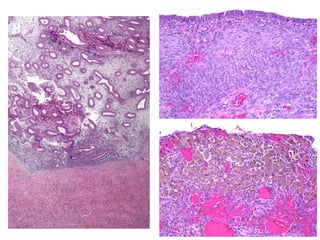

Carcinoma seroso do ovário

Tumor seroso atípico / borderline

Tumor seroso benigno (cistoadenoma seroso)

Cistoadenoma mucinoso

Carcinoma mucinoso do ovário